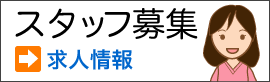

30分ほど前歯を削った後、色見本と照らし合わせながら調和のとれたカラーを決めていきます。

30分ほど前歯を削った後、色見本と照らし合わせながら調和のとれたカラーを決めていきます。